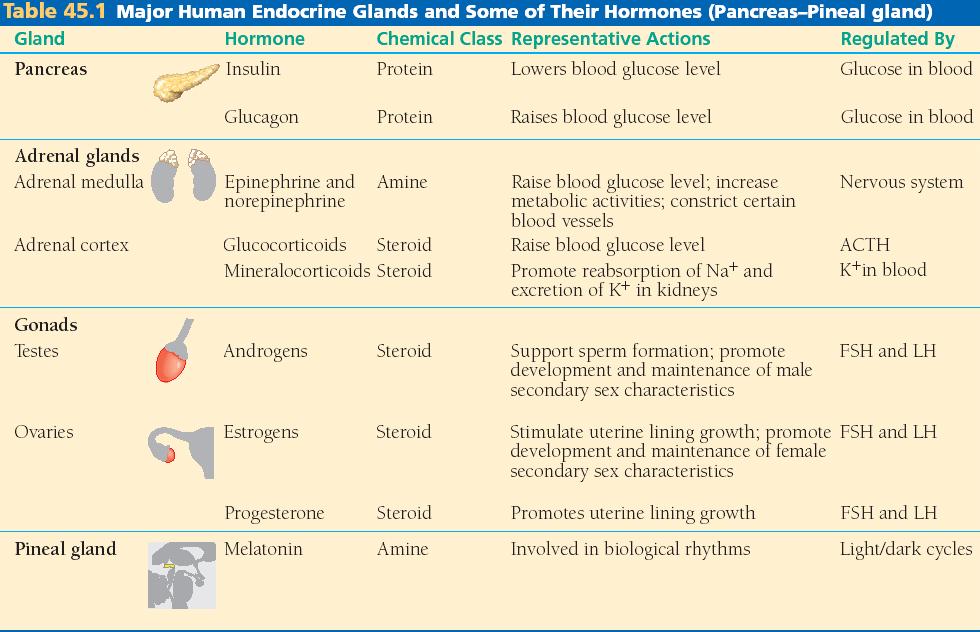

45_01bEndocGlandsPanc_T